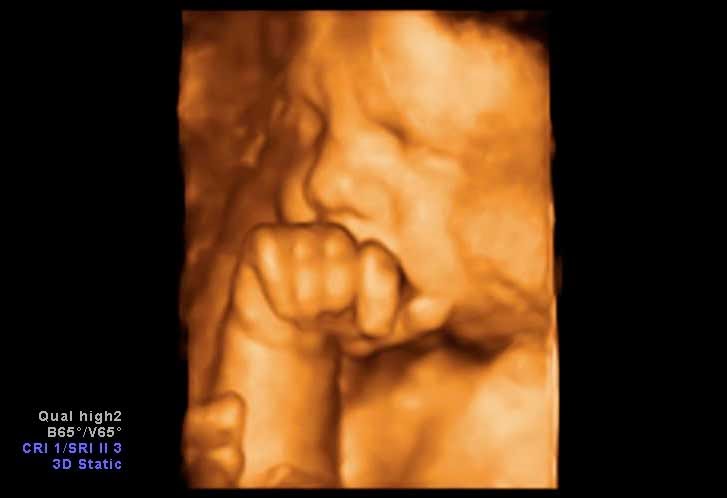

Diferencia Entre Eco 3d Y 4d

Diferencias Entre Ecografia 3d Y Ecografia 4d Ecografia 5d En

Diferencias Ecografia 4d 3d Y 2d